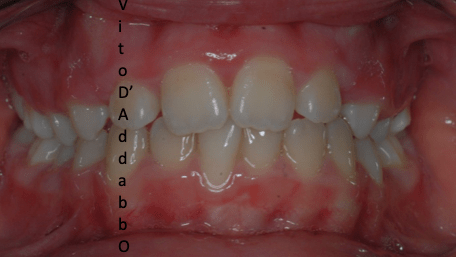

dopo – fase 1